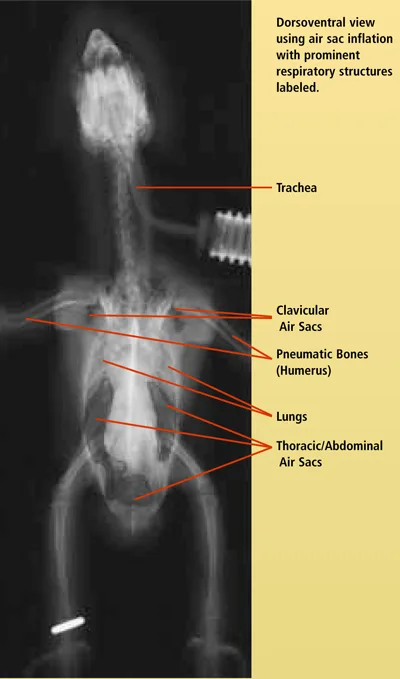

The avian respiratory system is extensive and complex. Becoming familiar with the normal presentation of respiratory anatomy through use of different imaging techniques will enhance a clinician's ability to make a diagnosis. This is the first of two articles using radiographic images and computed tomography (CT) to compare normal respiratory structures of the avian respiratory system. Note that the size of the patient dictates the size of the CT image. In this case, the patient is very small; thus, the images have become somewhat blurry with enlarging. Nevertheless, contrast is an important factor in CT imaging and the structures are quite clear. This article focuses on the body; the next part will address the head. For larger images, please click on the PDF icon at the top of the page to download the print version of the article in its entirety.

A ventrodorsal radiograph of a bird shows an inflated air sac system, highlighting increased contrast in the thoracic region. The image provides a clear view of the skeletal structure and respiratory anatomy, essential for veterinary assessment.